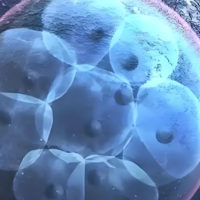

取卵和取精通常在同日进行,取出的卵子和精子在实践室中进行受精和培养。胚胎培养三至五天后,医生懂得挑选择一至两个优质胚胎移植入子宫。移植后仍旧要黄体支持治疗,约14天后即可进行妊娠检查。